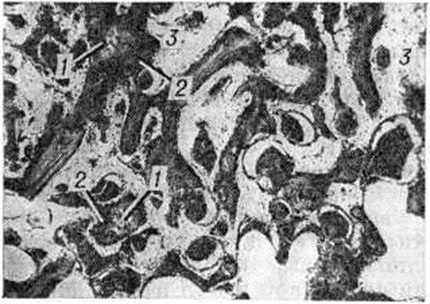

При точном сопоставлении отломков возможно прямое костное сращение с помощью интермедиарной костной мозоли, что именуют первичным костным сращением. Когда сращение отломков наступает после предварительного соединения их костно-хрящевой провизорной мозолью, на основе которой постепенно будет формироваться окончательная интермедиарная костная мозоль, говорят о вторичном костном сращении. Первичное костное сращение может произойти только в строго определённых условиях: при достаточном кровоснабжении отломков, точности их сопоставления, достаточности их обездвижения. Микрофотографии кости при первичном сращении в разные сроки консолидации представлены на рисунок 1 и 2.

В подавляющем большинстве случаев из-за трудностей обеспечения всех необходимых условий костное сращение бывает вторичным, при котором в разные сроки (но не ранее 6—8-й недель и до многих месяцев) после Переломы формируется окончательная костная мозоль. Такой вариант является проявлением адаптационных механизмов организма, направленных на восстановление целости кости в неблагоприятных условиях для заживления костных ран. Невозможность мобилизации таких приспособительных реакций приводит к несращению отломков повреждённой кости. Наиболее благоприятными для проявления адаптационных возможностей организма являются Переломы тех отделов костей, где имеется надкостница и окружающий её мышечный массив, например, диафизарные Переломы трубчатых костей. Переломы лишённых надкостницы эпифизов костей при отсутствии условий, необходимых для первичного костного сращения, не могут срастаться путём приспособительного вторичного костного сращения, поэтому без применения остеосинтеза отломки часто не срастаются, например, при медиальных Переломы шейки бедренной кости. Микрофотография кости при вторичном сращении представлена на рисунок 3.